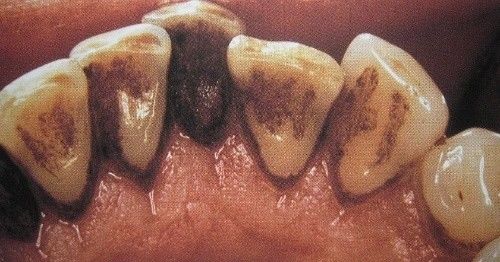

男性成年人喜欢喝茶、抽烟,造成牙齿表面色素沉着,很不美观

一个高职学校的学生,口腔内严重的牙结石,可能小时候没有刷过牙